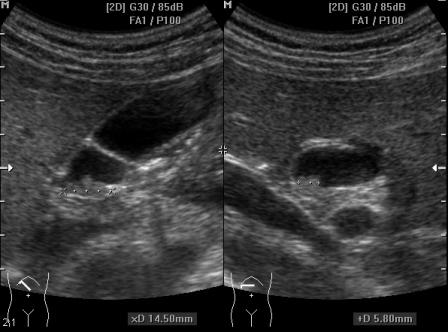

Ровно через месяц:

Написала "аденоматозный полип?".

Возможно, пациент поедет на КТ. Проследить случай, думаю, получится.

КТ никаких проблем в желчном пузыре не выявила.